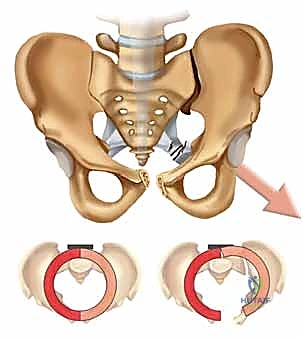

لفهم أهمية جراحة تثبيت المفصل العاني، يجب أولاً فهم التشريح المعقد لهذه المنطقة. يتكون الحوض من ثلاث عظام رئيسية تندمج معاً: الحرقفة (Ilium)، الإسك (Ischium)، والعانة (Pubis).

تلتقي عظمتا العانة اليمنى واليسرى في مقدمة الحوض لتشكلا المفصل العاني أو الارتفاق العاني (Pubic Symphysis). هذا المفصل ليس مفصلاً زلالياً حراً الحركة كالركبة أو الكتف، بل هو مفصل غضروفي ليفي مدعوم بشبكة كثيفة وقوية جداً من الأربطة. يسمح هذا المفصل بحركة طفيفة جداً (حوالي 2 ملم انزياح ودرجة واحدة من الدوران) لامتصاص الصدمات أثناء المشي، ويتمدد بشكل طبيعي لدى النساء أثناء الولادة.

عند حدوث قوة قاهرة تفوق قدرة تحمل هذه الأربطة، يتمزق المفصل وتنفصل عظام العانة عن بعضها، وهو ما يُعرف طبياً بـ "كسر الكتاب المفتوح" (Open Book Fracture) إذا تجاوز الانفصال 2.5 سم. هذا الانفصال يؤدي إلى عدم استقرار كامل في الحلقة الحوضية.